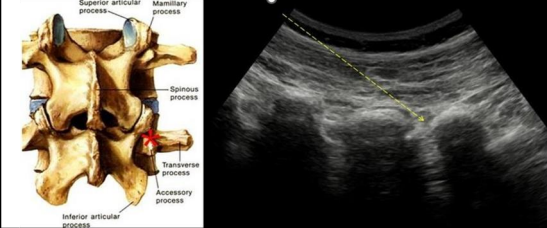

Figure 5

Ultrasound Images of the paraspinal region with a red asterisk locating the targets in the inter apophyseal and facet valleys, where the needle is inserted in a proximal to distal fashion with a dotted arrow indicating the path.